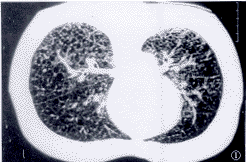

患者既往体健,无特殊病史;以前月经正常,近2月来周期缩短,行经期延长达10天;体格检查:无阳性发现;血气分析各项指标及血雌二醇均在正常范围。胸部X线:肺容积增大,双肺呈间质纤维化改变。胸部CT:双肺野透亮度增高,并可见多个大小不等透亮区,双肺分布较均匀,囊状透亮区边缘可见薄壁,透亮区之间可见正常肺组织(图1)。肺功能:明显阻塞性减退,肺弥散功能重度减低。腹部B超:肝、胆、脾、肾脏、子宫等均未见异常。纤支镜检查:双肺支气管粘膜充血明显,于右肺下叶行肺活检。

图1 CT超薄扫描显示双肺弥漫分布的细网格状影